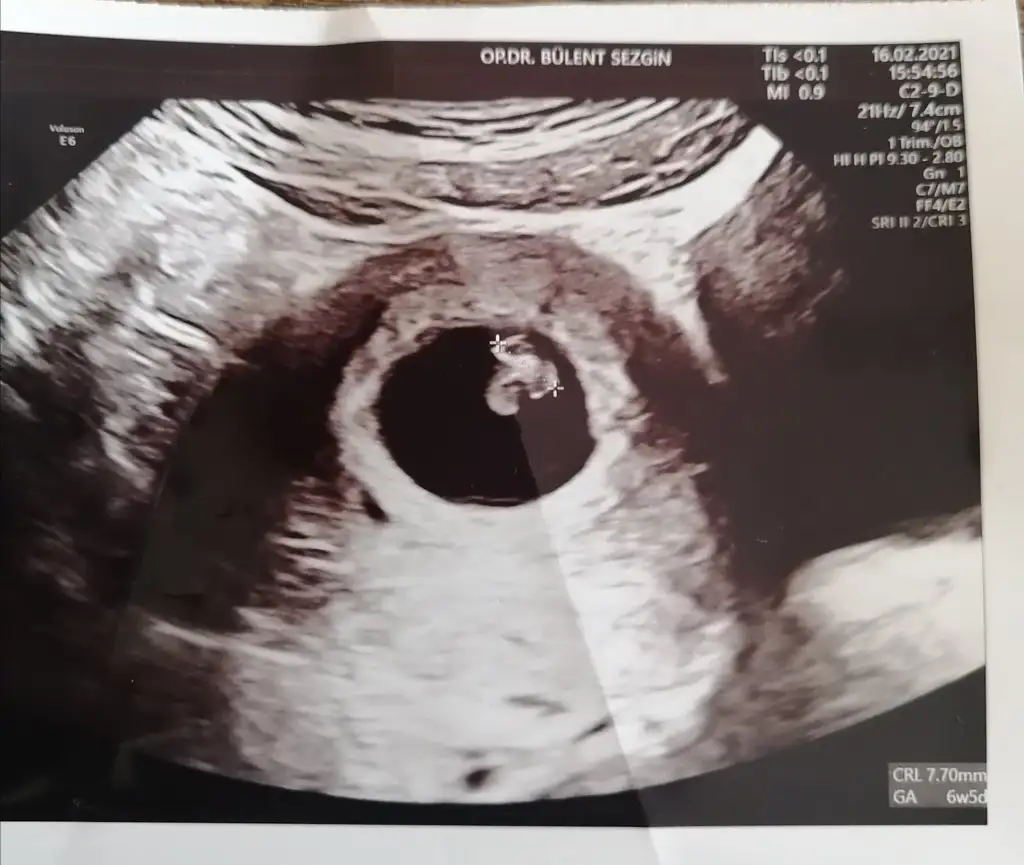

6+5 ve 7+6 acaba nedir çok merak ettim 🥰 T Takitoki

• IMG_20210216_173232.webp

IMG_20210216_173232.webp

32,7 KB · Görüntüleme: 116

6+5 7+6 karından usg 😊 yazmayı unutmuşum tekrar attım T Takitoki